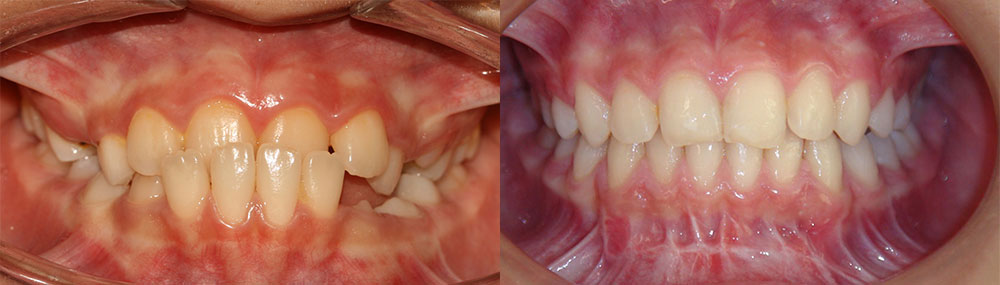

ارتودنسی دندان قبل و بعد، توسط پروفسور جمیلیان

برای دیدن نمونه کارهای ارتودنسی بیشتر می توانید به گالری تصاویر قبل و بعد ارتودنسی مراجعه کنید. در این قسمت تعداد بیشتری از این نمونه کارهای ارتودنسی دندان و فکین را مشاهده خواهید نمود. بسته به ناهنجاری فک و دندان درمان های متفاوتی در نظر گرفته می شود. در اینجا عکس دندان هایی که نیاز به ارتودنسی دارند را مشاهده می کنید. ممکن است بیماری شما نیز شبیه به یکی از این موارد باشد. در این صورت می توانید بهبودی و درمان های موفق را در این قسمت به وضوح مشاهده نمایید.